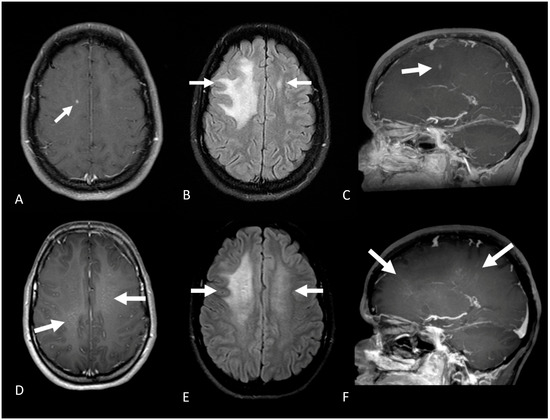

| Location | N/A 1 | Bilateral PVWM lesions, including the amygdala and hippocampus | Right occipital lobe, right precentral gyrus, and multiple small lesions in PVWM | Subcortical and PVWM lesions in the right frontoparietal and insular lobes | Right parieto-occipital subcortical and PVWM, extending to the splenium |